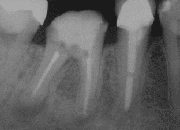

X-Ray of a tooth after root end surgery

A root end surgery, also known as apicoectomy (apico- + -ectomy), root resection, retrograde root canal treatment (c.f. orthograde root canal treatment) or root-end filling, is an endodontic surgical procedure whereby a tooth's root tip is removed and a root end cavity is prepared and filled with a biocompatible material.